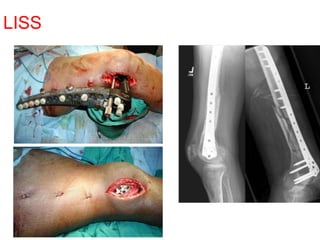

LISS System

 Preshaped plates with

self drilling self tapping

screws with threaded

heads.

 Through a small incision

(using this jig ) plate is

slid along the bone

surface. position of plate

and wire are checked

radiologically before

insertion of metaphyseal

screw .

LISS-Less Invasive Stabilization

System

LISS